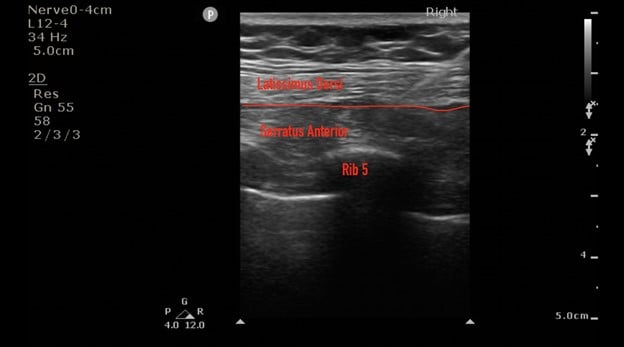

Target directed pain management therapies to the causal nerve, bone, or tendon provide a unique way to provide analgesia while decreasing the need for opiate consumption. The Serratus Anterior Plane Block (SAPB) is a commonly used regional block that was developed as a safer alternative to the thoracic paravertebral and neuro-axial thoracic epidural.3 It provides hemi-thoracic analgesia by blocking the thoracodorsal, long-thoracic, and intercostal nerves from T2-T9. Herein, we describe the use of a SAPB for non-emergent thoracostomy for the treatment of a spontaneous pneumothorax. The patient was a 62 year old male who presented to the ED with worsening dyspnea and was found to have a moderate-sized right-sided spontaneous pneumothorax without midline shift. The decision was made to pursue the placement of a pig-tail catheter and admit for observation. Prior to pig-tail placement, a SAPB was performed to optimize intra-procedure and postoperative pain control. The SAP block was performed by placing a linear transducer in the coronal plane in the mid-axillary line, starting at the clavicle and moving caudal to the fourth rib space, wherein the serratus anterior can be identified superficial to the ribs and deep to the latissimus dorsi. A mixture of 15 mls of Bupivacaine 0.5% and 15 mls of saline for a total volume of 30 cc was injected into the fascial plane located between the serratus anterior and latissimus dorsi. This was well below the toxic dose of 2-2.5mg/kg.4 The patient developed analgesia extending from approximately T2/T3 to T8, and the patient tolerated pigtail catheter placement at the fourth intercostal space. The patient required no additional pain medication after the initial placement and had good pain control after being evaluated two hours and six hours after the block was completed. The chest x-ray is provided below.

Ultrasound images courtesy of Christopher Moore, MD